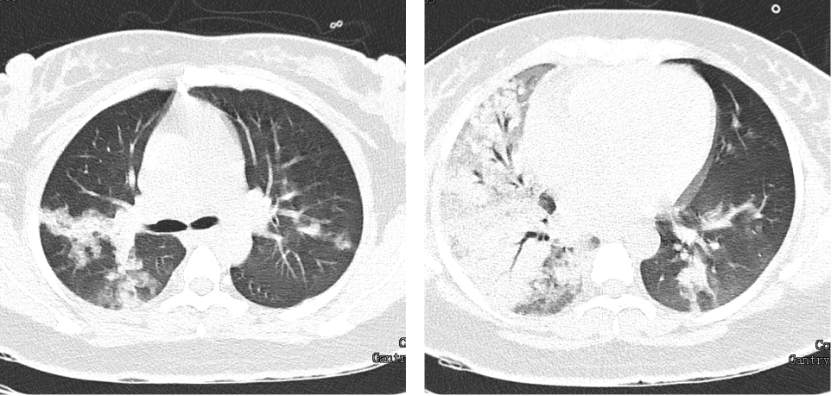

简单介绍一个病例:35岁女性,因发热咳嗽胸闷1周入院,门诊查甲流咽拭子(+),诊断为流感病毒感染,予奥司他韦抗病毒治疗。抗病毒治疗后复查甲流咽拭子已转阴,但仍发热,咳嗽胸闷加重,查胸部CT如下:

万古霉素治疗3天无好转,患者仍高热不退,体温39度以上,伴气促与脉氧下降,查血气示I型呼吸衰竭,复查痰培养仍为MRSA(+),下一步怎么办?